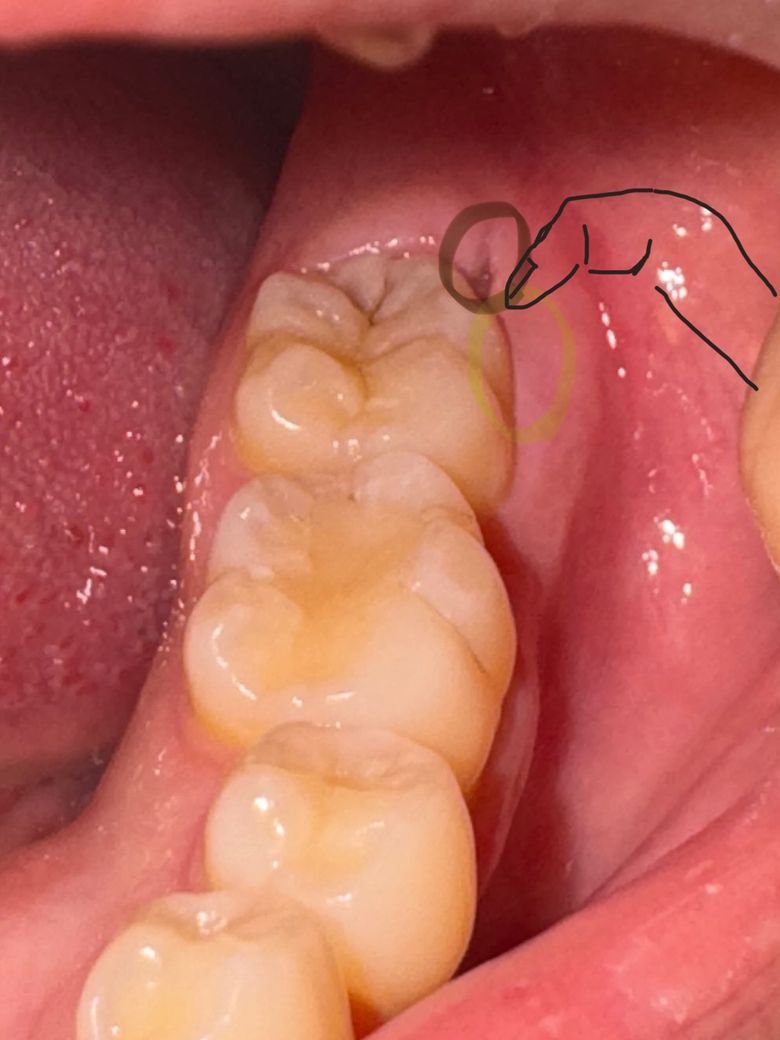

사랑니가 나려고하는 자리에 구멍 있음(???)

오늘 밥먹고 저 부분에 무언가 낀듯한 불편감을 느끼고 봤더니 저런 구멍(갈색동그라미)이 나있었고

뭔가하고 손가락 부분을 옆으로 당겨보니,

결석이 되기 직전? 찌꺼기가 꽤나 나왔습니다 ㅜㅜ 바닥엔 치아색과 같은게 있어서 사랑니가 아닌가 싶어요..

이 부분(갈색-노란동그라미)에서 악취가 나기도 했구요… 나름 부드럽게 제거를 했어요..

저 구멍이 매복 사랑니가 있어서 그런거죠…?

사랑니가 잇는 자리에 구멍이 생긴건 잇몸이 내려가면서 잇몸이 얇아지게되면서 그러는겁니다. 계속해서 잇몸이 얇아질꺼고 염증이 생길수도 잇으니 불편하시면 발치를 하시는게 좋을것같습니다.

네 하방에 매복 사랑니가 있고, 사랑니로 인해 잇몸이 종종 붓고 아플 수도 있습니다. 이는 위생관리가 안된다면 증상은 더 심해질 수 있고요. 불편함이 지속된다면 사랑니 발치를 고려해보셔야합니다.

사랑니 때문일 가능성이 매우 높습니다. 한동안은 괜찮겠지만 맹출 방향으로 볼 때 염증 발생 가능성이 높고 잇몸에 일부분만 덮여있어 충치 가능성도 있는데요. 예방적으로 발치해주는 것을 추천드립니다. 어렸을 때 뼈의 탄성이 좋고 치유가 잘 되어 발치가 수월하기 때문입니다.